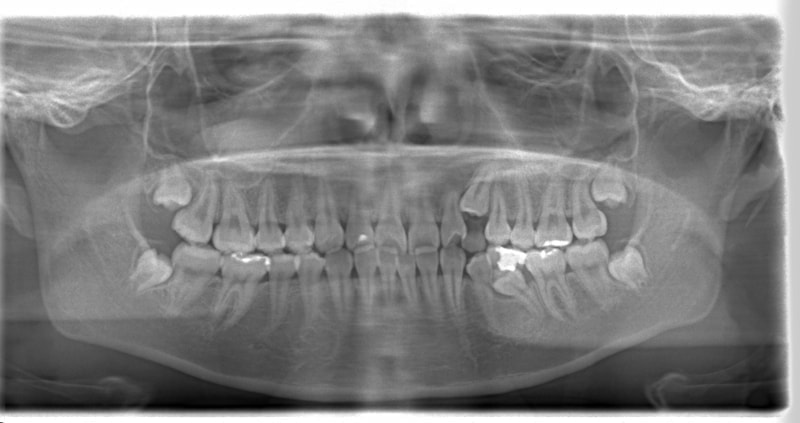

左上3番左下5番埋伏歯

治療前